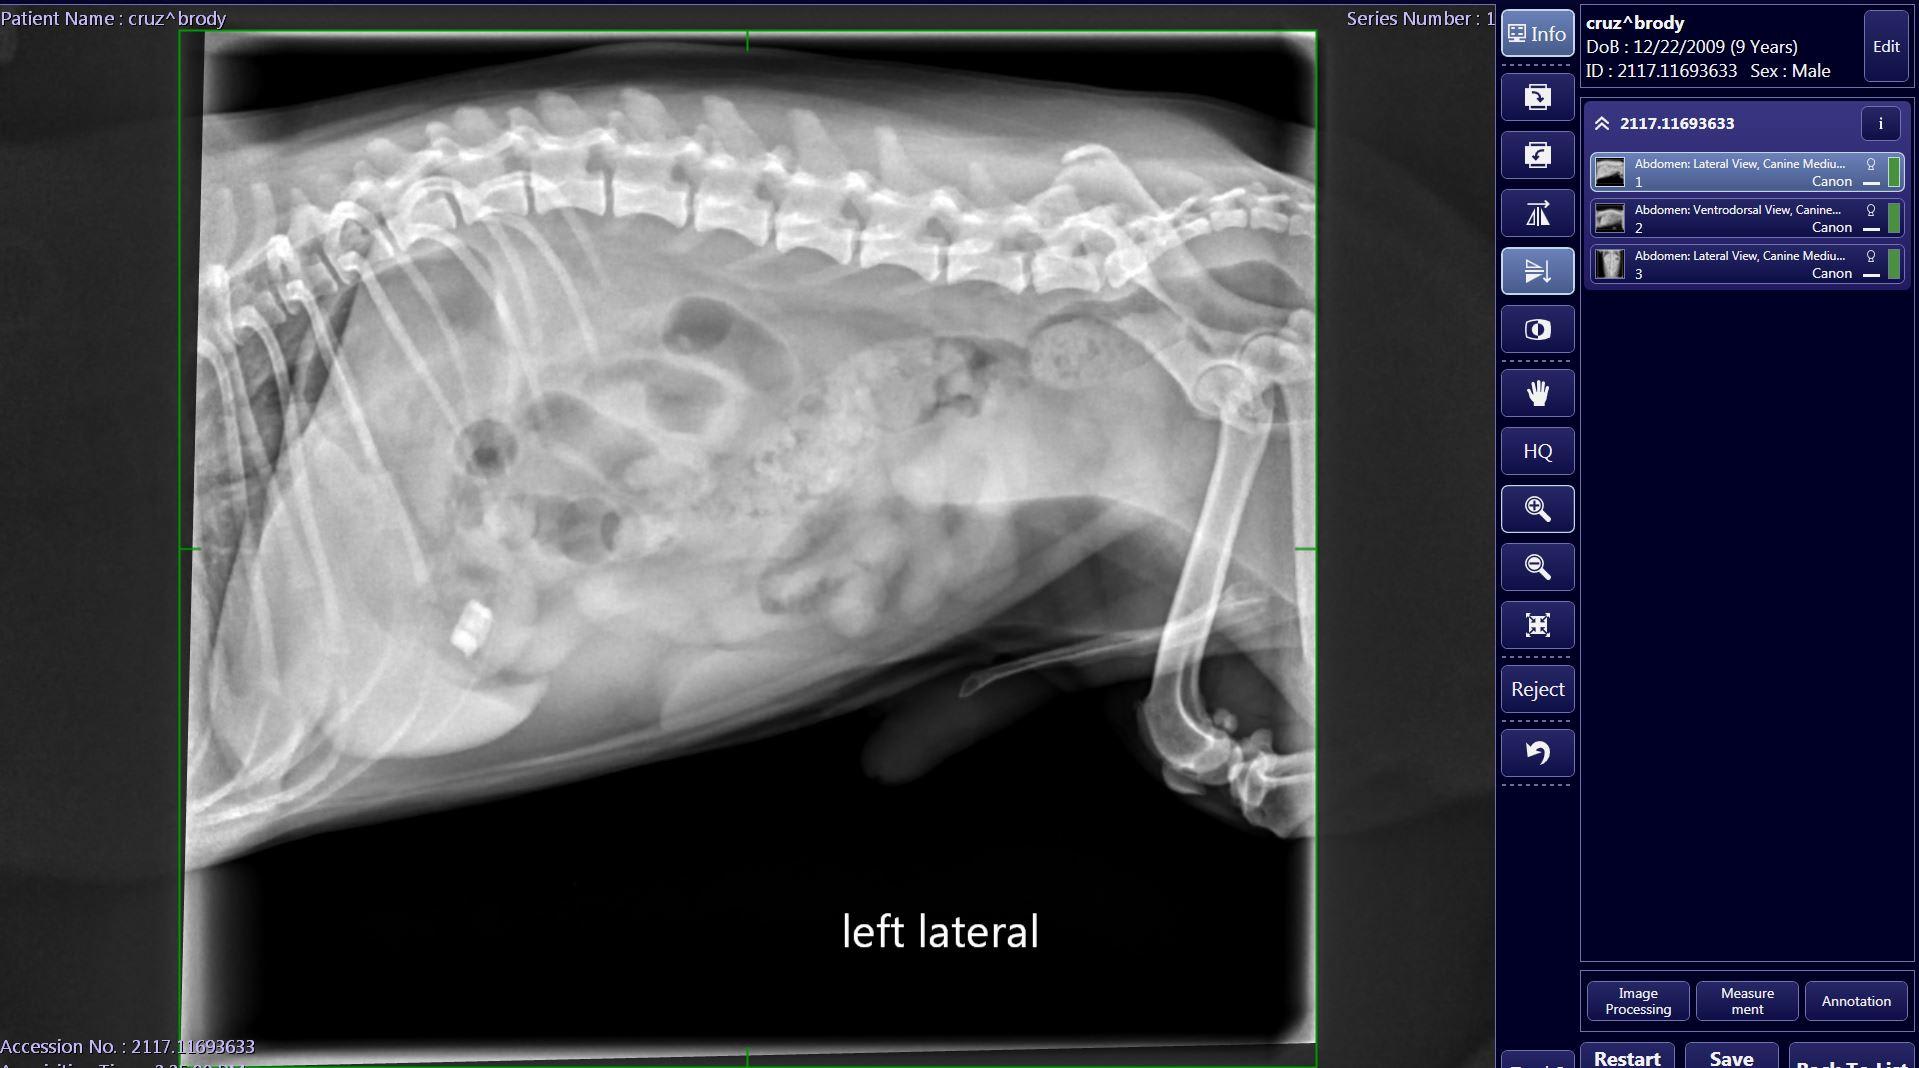

my dog Swallowed a small piece of wrapper from a salami that has a small metal piece attached on 12/18. He started throwing up yellow bile for about four days I took him in on Saturday for x-rays which showed the object still in his stomach. He has been acting normal, he eats, drinks water he goes on walks and pees/poops fine but the object has not moved from the stomach after I took him to the vet once again this Monday, 12/24. Vet recommended to wait till Jan 2 but I’m afraid that’s too long.